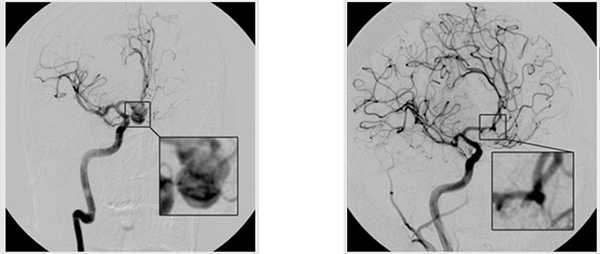

аневризма до/после операции

Возможные осложнения

Осложнения при клипировании аневризмы составляют не более 8%. Однако определенный риск все равно существует, поэтому пациент должен быть тщательно осведомлен о всех возможных последствиях. Последствия могут быть как незначительными, так и серьезными, и даже жизнеугрожающими.